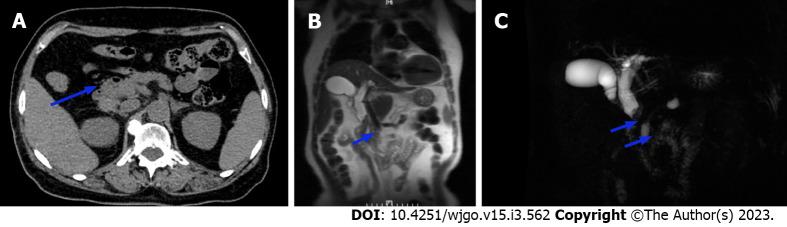

The patient was a 75-year-old woman who had experienced recurrent chills with nausea and vomiting for 3 mo. Computed tomography, magnetic resonance imaging, endoscopic ultrasonography and endoscopic retrograde cholangiopancreatography led to the diagnosis of malignant tumor of the CBD. The patient ultimately underwent cholecystectomy, CBD resection, and choledochojejunostomy. Postoperative pathological examination revealed carcinosarcoma of the CBD, and the latest follow-up showed that the patient is recovering well. Based on previous case reports, some carcinosarcoma has ossification characteristics in imaging. If it is misdiagnosed as biliary calculi, the use of laser lithotripsy in surgery may lead to tumor diffusion. Choledochoscopy and narrow band staining of mucosa are very important for diagnosis.

We herein present a rare case of carcinosarcomas of the CBD, we found the tumours may have imaging features of polypoid growth and ossification only when the sarcomal components are bone differentiation, while show soft tissue shadow when non bone differentiation. Confirmation of diagnosis depends greatly upon postoperative pathological examination and the adjuvant treatment has not been established, which leads to the poor prognosis.